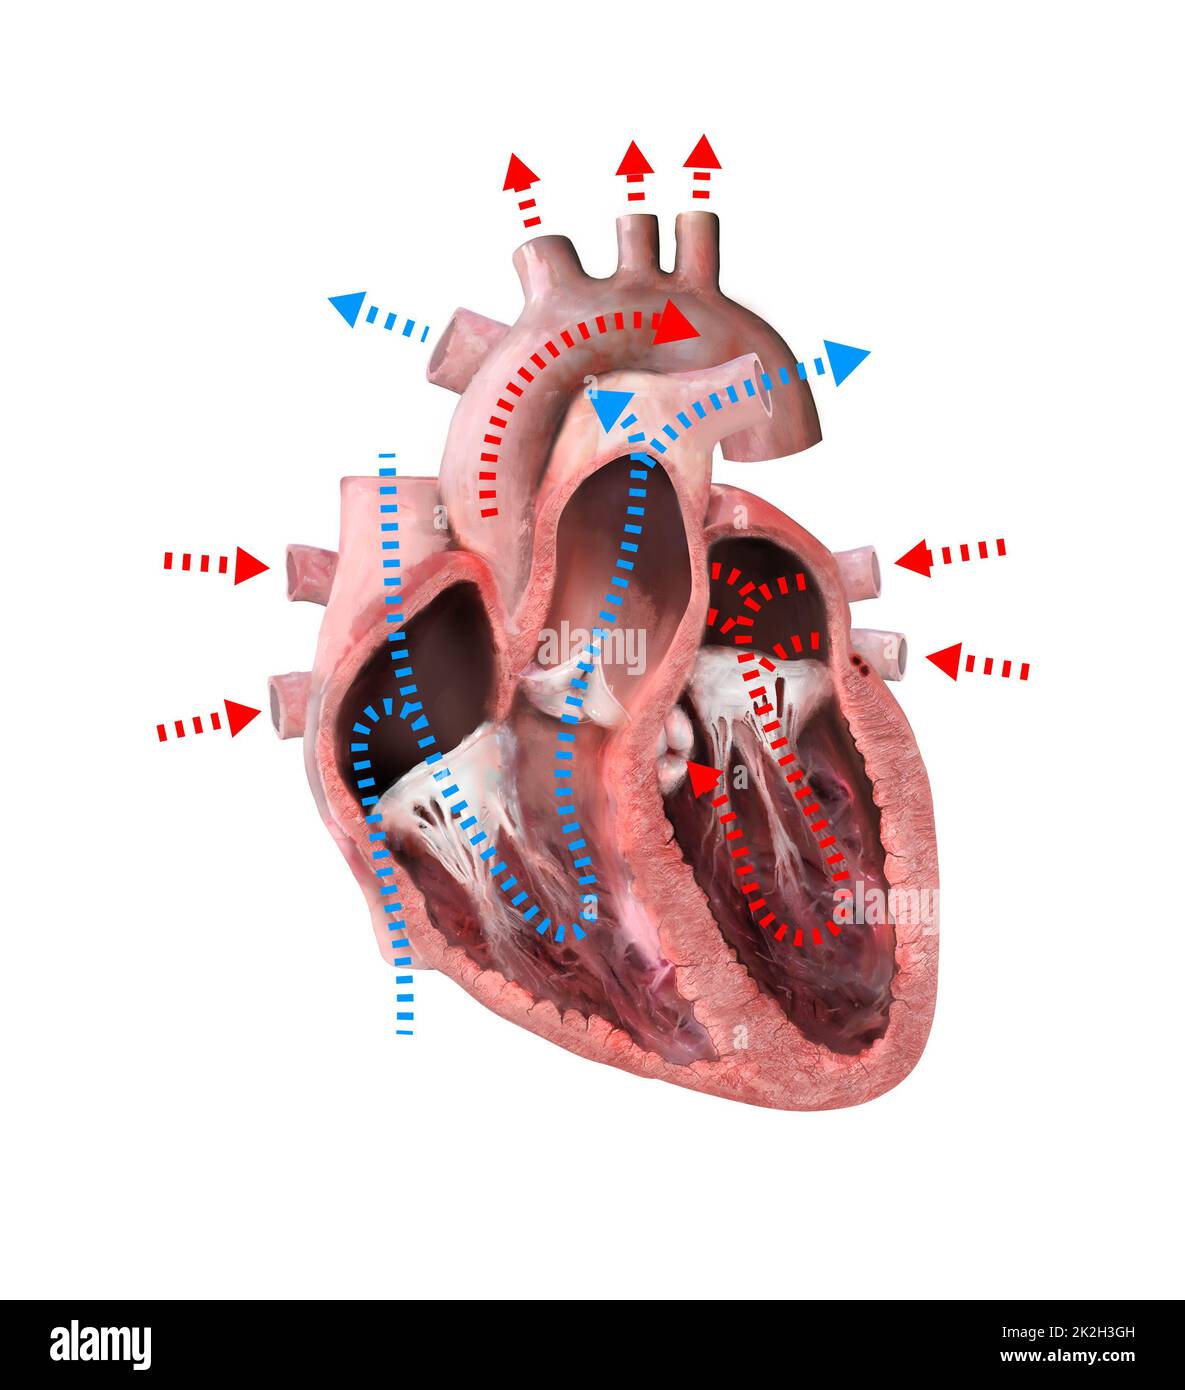

human heart anatomy. Educational diagram showing blood flow with main parts labeled. illustration 3d render Stock Photohttps://www.alamy.com/image-license-details/?v=1https://www.alamy.com/human-heart-anatomy-educational-diagram-showing-blood-flow-with-main-parts-labeled-illustration-3d-render-image483495617.html

human heart anatomy. Educational diagram showing blood flow with main parts labeled. illustration 3d render Stock Photohttps://www.alamy.com/image-license-details/?v=1https://www.alamy.com/human-heart-anatomy-educational-diagram-showing-blood-flow-with-main-parts-labeled-illustration-3d-render-image483495617.htmlRF2K2H3GH–human heart anatomy. Educational diagram showing blood flow with main parts labeled. illustration 3d render